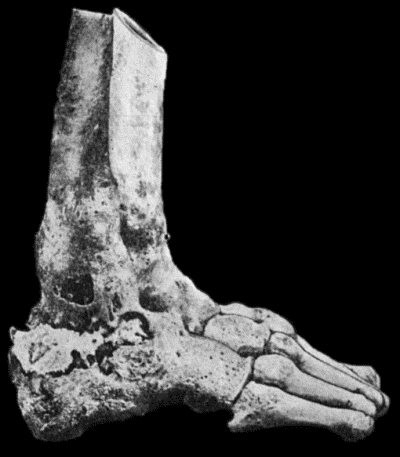

128 32.Mycetoma, or Madura Foot

458 127.Advanced Tuberculous Disease in Region of Ankle

459 128.Tuberculous Dactylitis